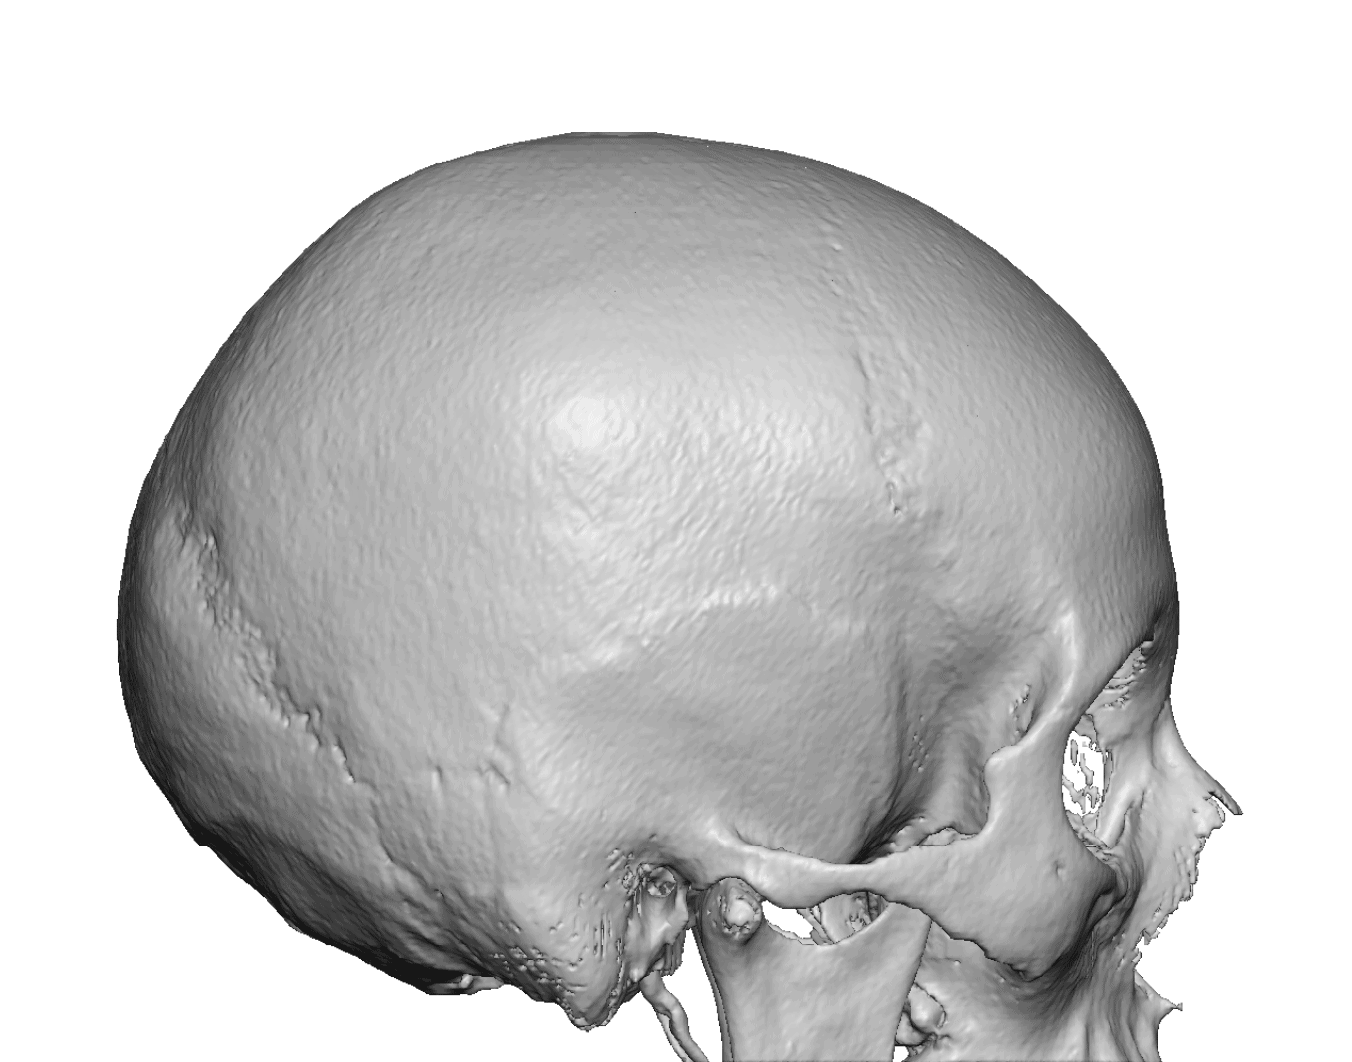

Patient 28

Desire for rounder shape to the top of the head from a congenital parasagittal deficiency skull shape.

Custom skull implant designed to fill in the parasagittal deficiencies.

Desire for rounder shape to the top of the head from a congenital parasagittal deficiency skull shape.

Custom skull implant designed to fill in the parasagittal deficiencies.